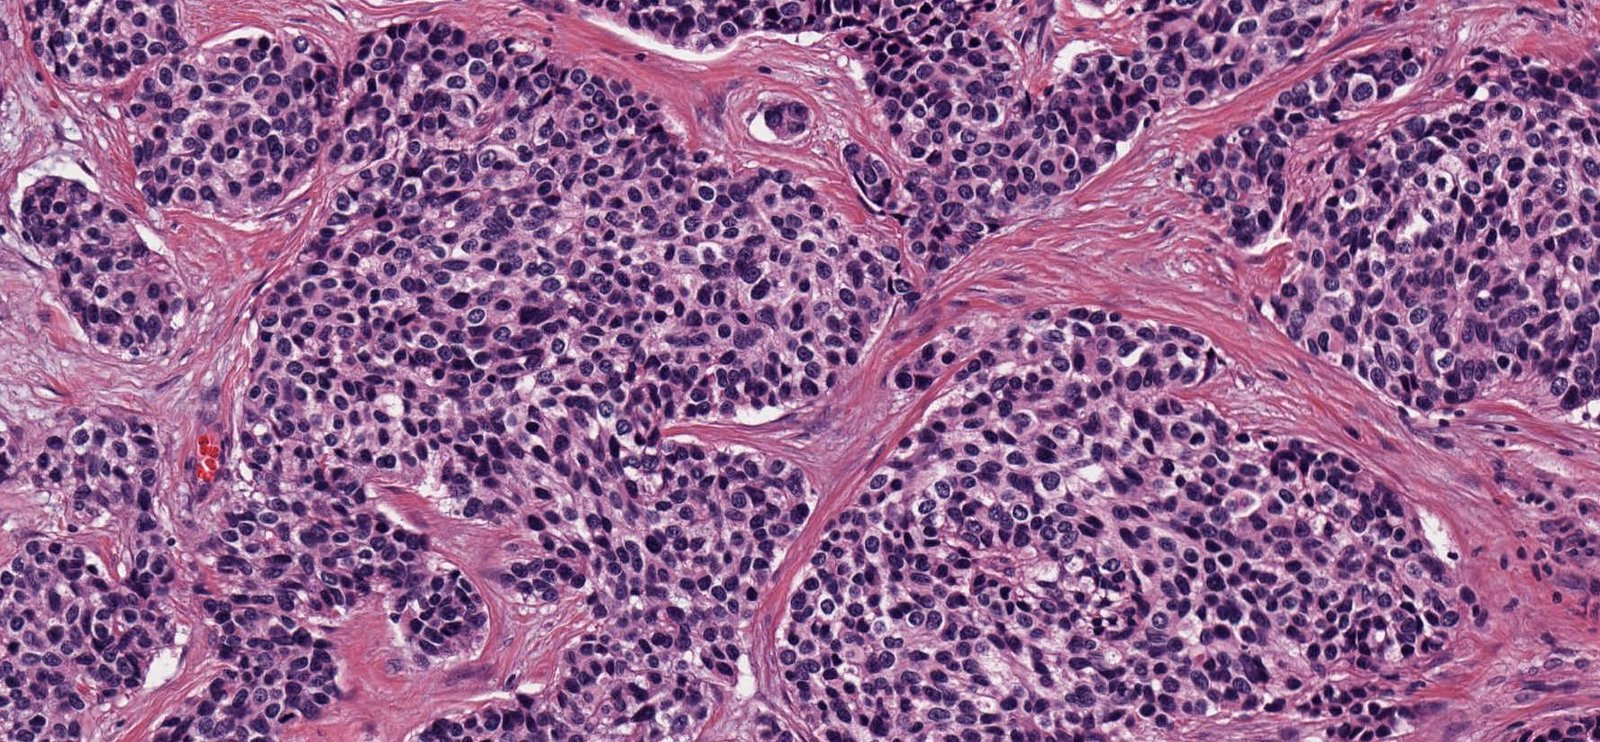

Case: AbdominalMass

Final Diagnosis: